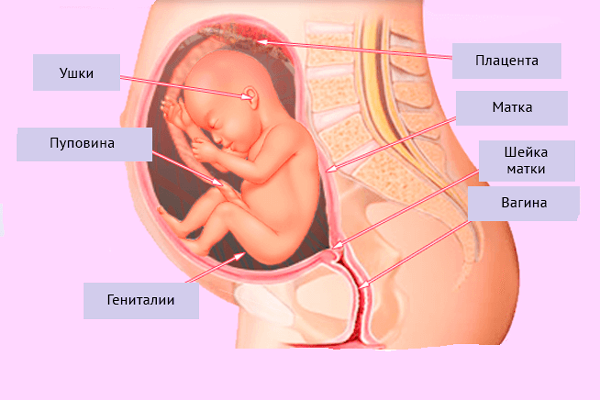

25 недель беременности: Как выглядит будущий малыш